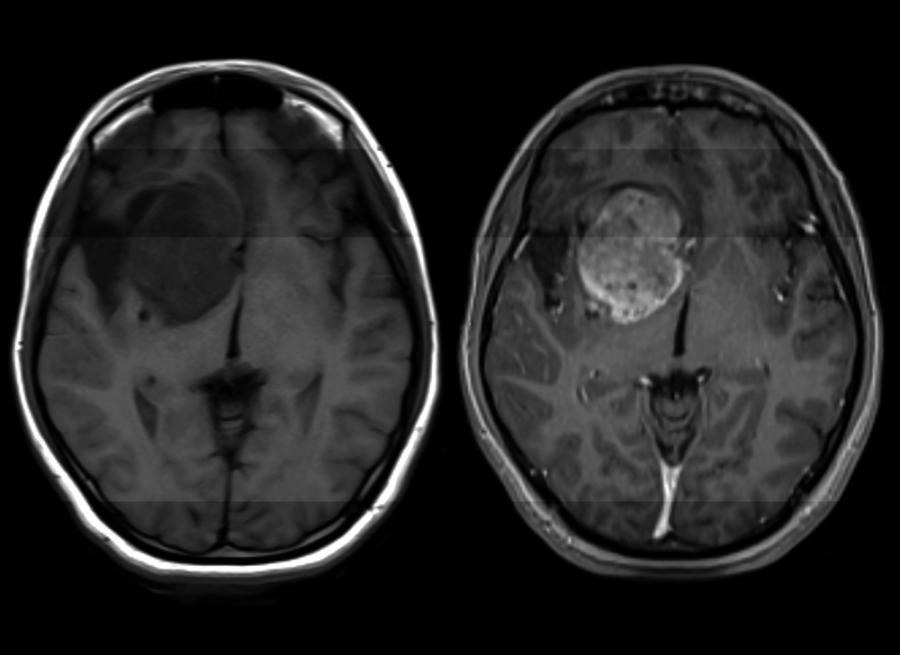

За този смъртоносен рак на мозъка няма лек. Учени обаче откриха как да го преборят

Всяка година близо 250 000 души са диагностицирани с глиобластома. Това е агресивен и непредсказуем рак на мозъка, за който няма превенция. На всеки един от тези пациенти им остава средно от 12 до 18 месеца (без лечение този период намалява значително). Едва 1 на 20 ще бъде жив в следващите 5 години.